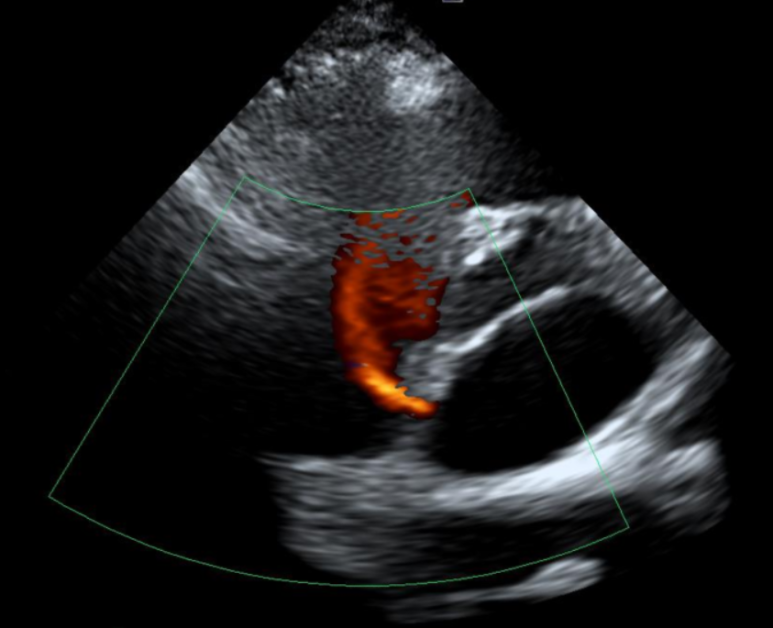

2. 심장초음파(도플러)

• 우심방과 좌심방 사이의 벽의 결손을 통해 혈류가 새는 현상 우심방과 좌심방 사이의 벽의 결손을 통해 혈류가 새는 현상